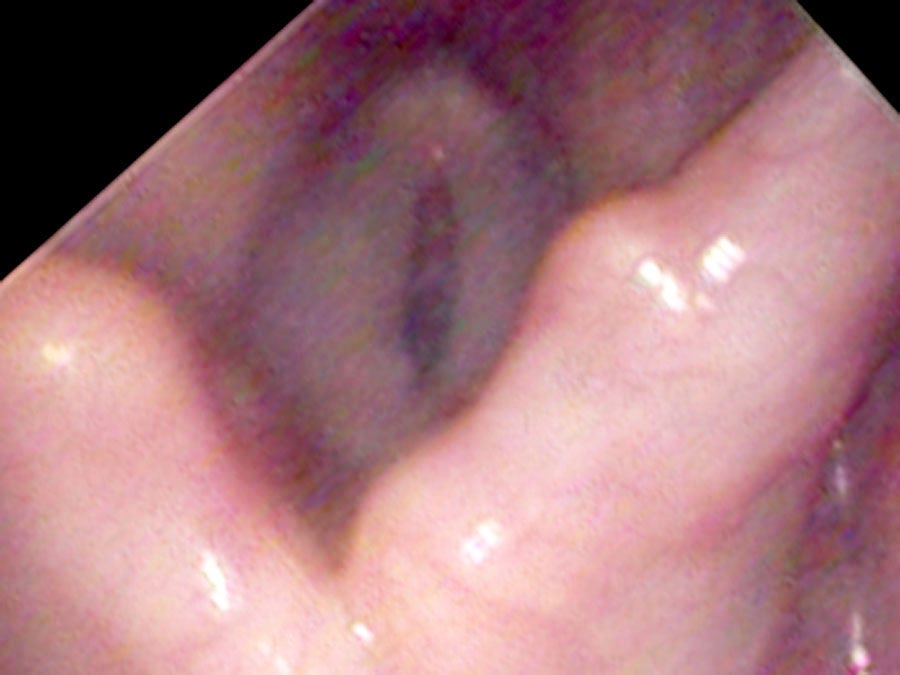

On endoscopy, there is a surprisingly large lump on the right vocal process — a yellow ball of tissue sitting just above an ulcerated groove in the cartilage.

It really isn’t a growth. It is a collection of blood vessels wound into a little ball — what surgeons call “proud flesh” when it forms on the outside of the body.

There is one particular type of vocal cord lesion that may start with a temporary pain and is located at the back of the larynx — most commonly on the cartilage called the vocal process of the arytenoid, right at the end of the vibrating portion of the vocal cord. It is not really a growth. Rather it is a collection of blood vessels wound into a little ball — called proud flesh when it forms on the outside of the body. When something traumatizes the mucosa, eroding through it and exposing the cartilage, an ulcer forms. Then granulation tissue heaps up around the traumatized point as a reaction to an open wound exposed to the bacteria of the mouth and throat.

From injury to resolution, granulomas follow a predictable evolution. New ulcers from overuse initially split into two parts where the opposite vocal process rests in a groove during closure. Gradually, granulation tissue heaps up around the traumatized point, forming a mass. In the middle of their lifespan granulomas become yellow or red and round. Later the mass tends to harden, become white and spherical, and the base narrows to a stalk. At this stage the granuloma may flip up out of the way during phonation and no longer impairs closure — so vocal capabilities testing can return to normal even while the granuloma is still present.